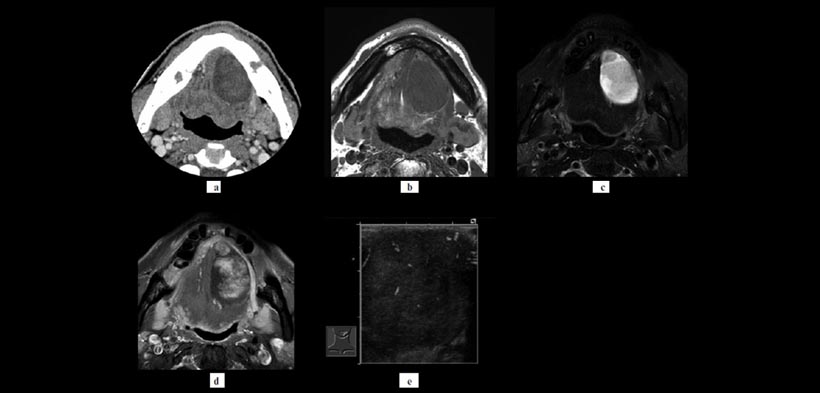

Figura 1. Paciente masculino de 62 años de edad, se había dado cuenta de una inflamación indolora en el piso izquierda de su cavidad oral hace 1 mes. El diagnóstico histopatológico fue un schwannoma. (a) La masa de aislamiento en el piso bucal izquierda era ovalada, bien circunscrito y heterogéneo con baja captación de contraste e la tomografía computarizada (aproximadamente 14 HU). En la resonancia magnética (RM) (b) T1 ponderado imágenes (T1 SIO) mostraron isointensidad homogénea. (c) T2 imágenes ponderadas (T2 SIO) mostró periféricamente alta intensidad y centralmente intensidad relativamente baja, mientras que mostró gadolinio T1 SOF se mostró el ” signo de destino” (d). Lobulación se ve en la figura (c) y (d). (e) Las imágenes de una ecografía Doppler de potencia por el abordaje intraoral demostraron vascularización moderada de la lesión.